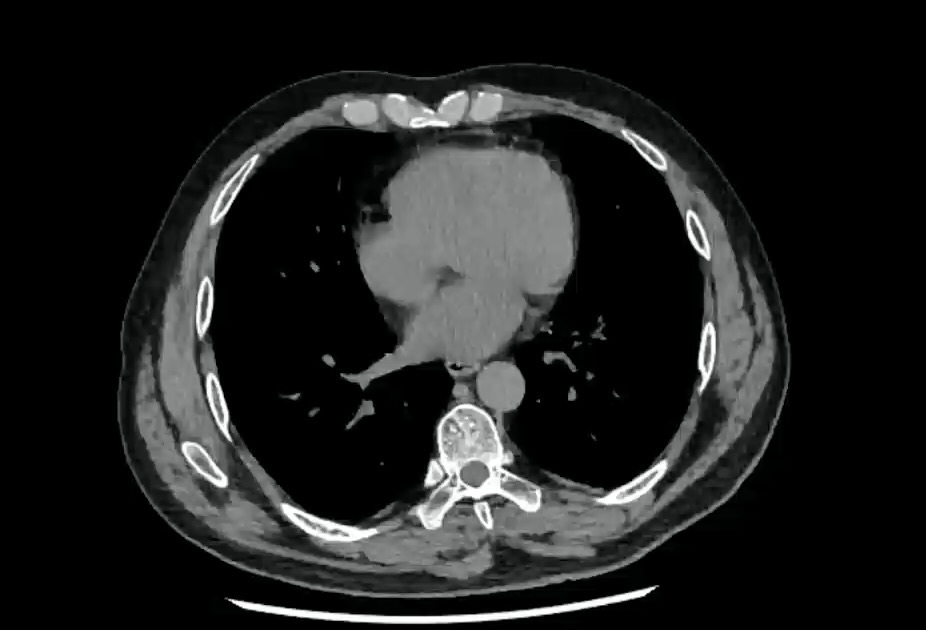

【患者信息】:男,43岁。

【主诉】:自诉吃完麻辣烫和山楂后,腹痛腹胀一天。

【检查】